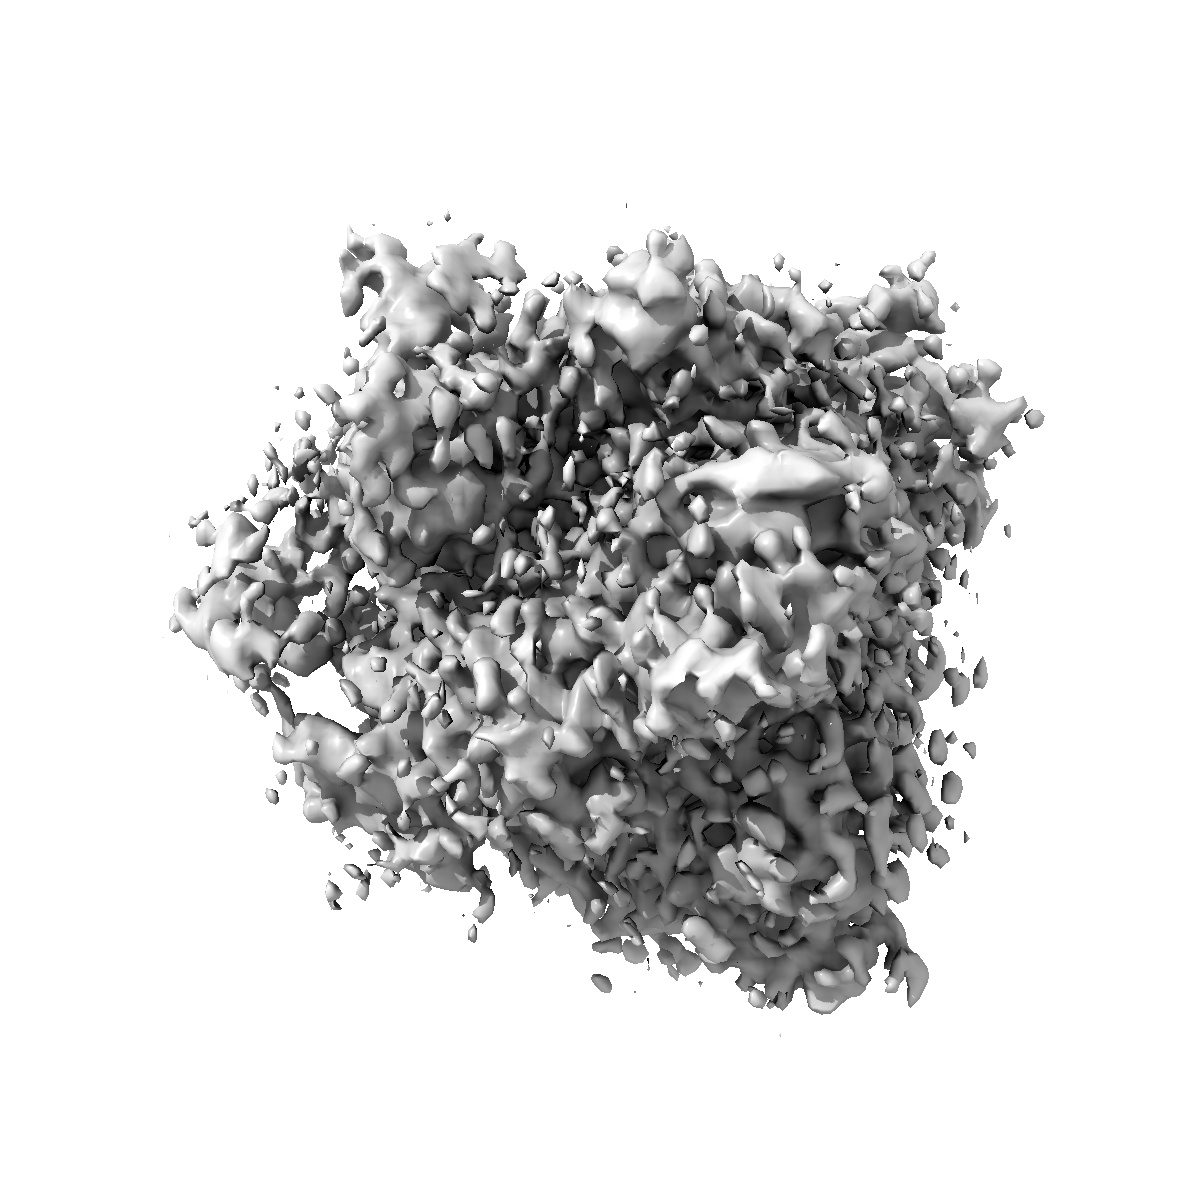

Cryo-EM structure of Fas-FADD complex

Sample: Human Fas-FADD DD complex

Fitted models: 9ncq

Assembly and activation of the death-inducing signaling complex.

Fosuah E , Shen Z , Xie J , Wang C , Lin Q, Fu TM

(2025) PNAS , 122 , e2504819122 - e2504819122